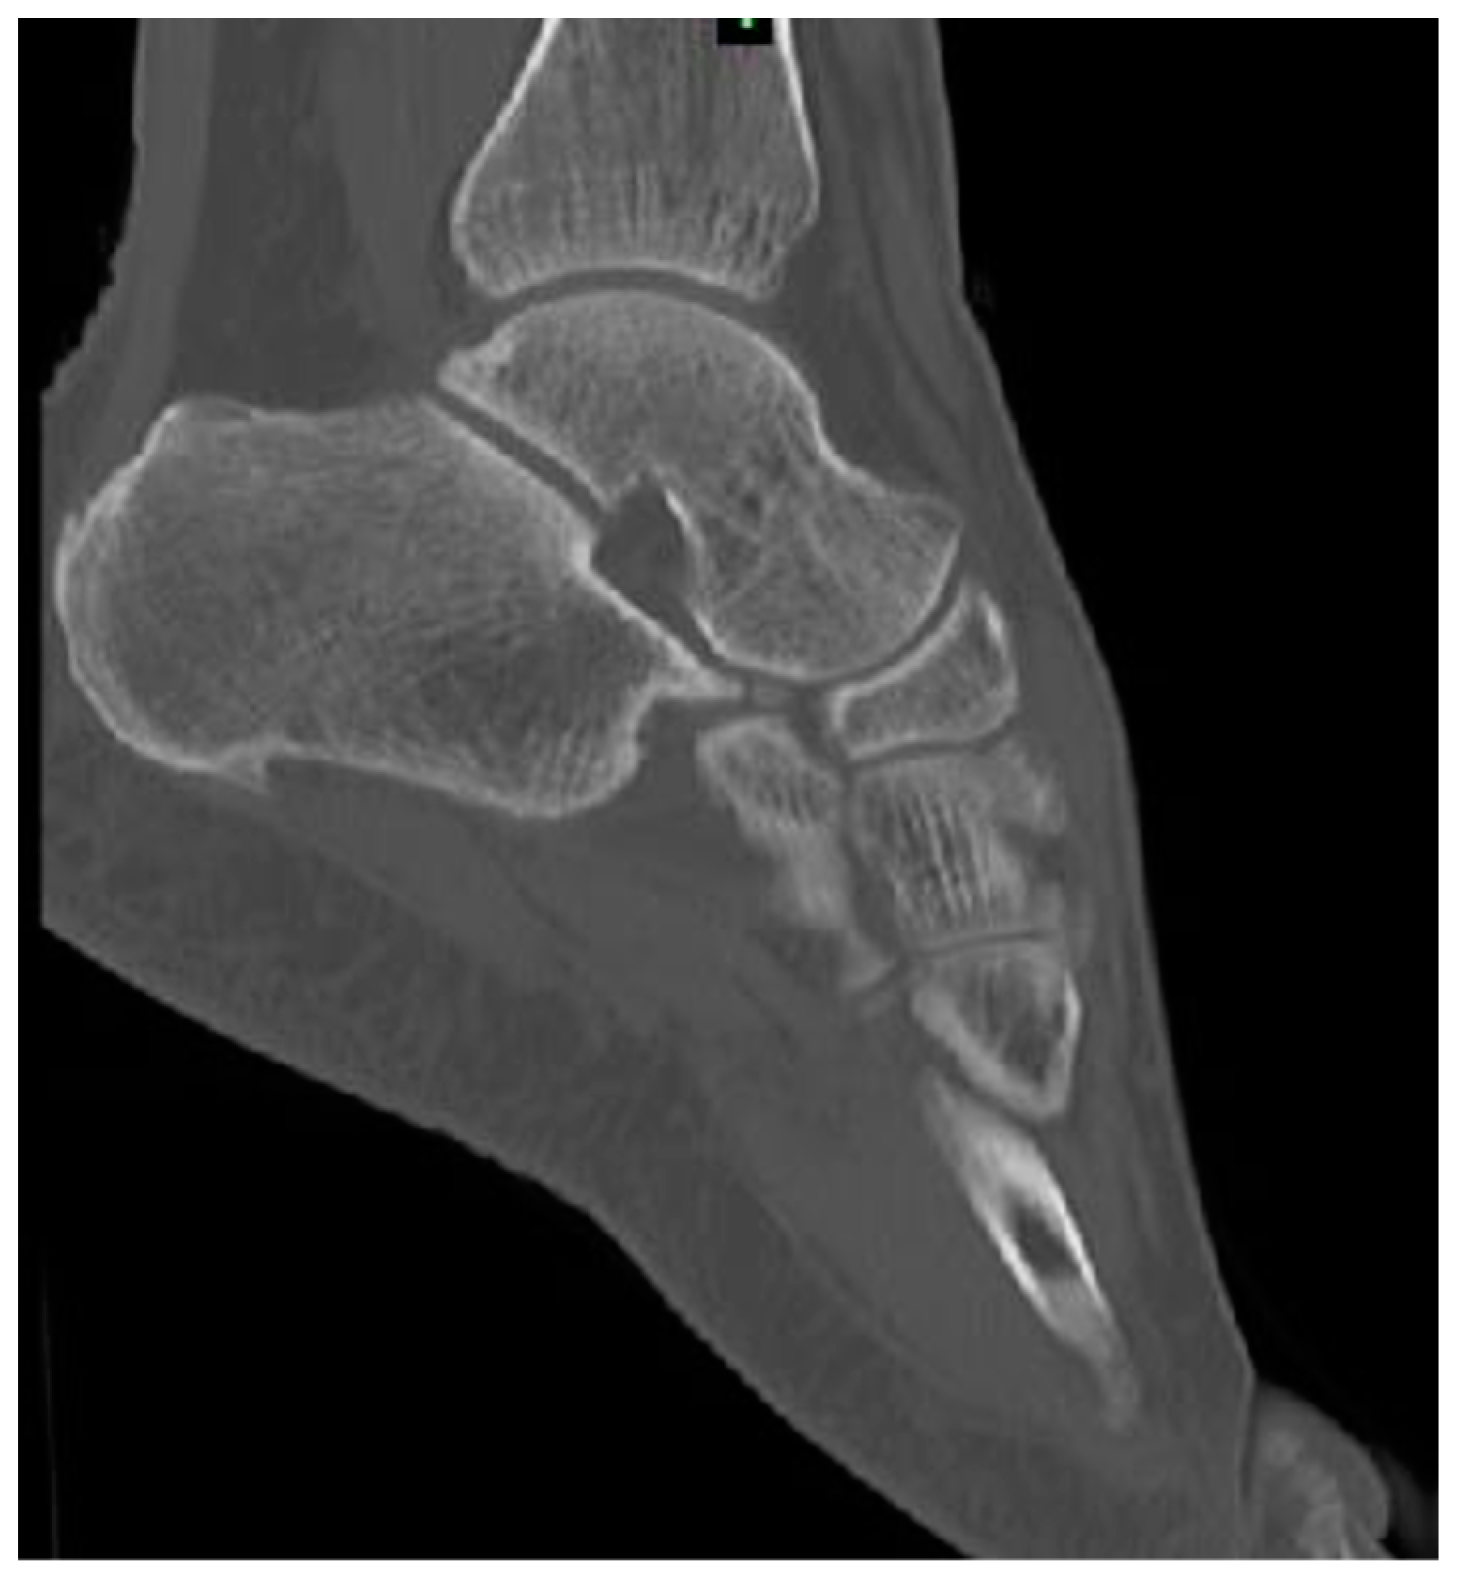

2. Numerical Bone Modelling

4.1. Numerical Model